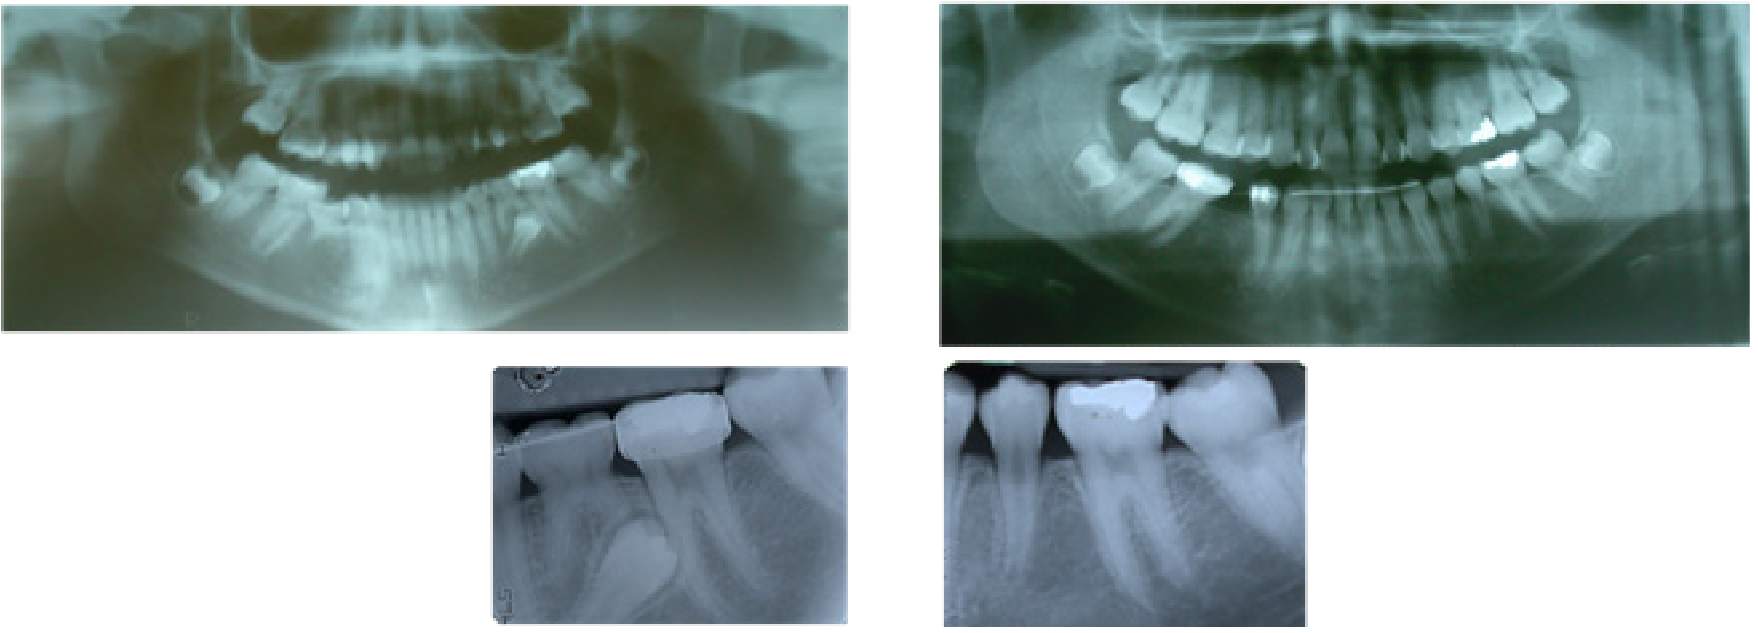

Caso 1. Paciente femenino de 13 años referida por el odontopediatra para consultar la posición de los caninos superiores. Los padres refieren perfecto estado de salud y que la paciente no tuvo tratamiento de ortodoncia u ortopedia previo, durante la anamnesis se reportó solamente alergia al maní. Entre sus antecedentes familiares, los padres fueron tratados ambos con ortodoncia y la madre refiere agenesia de terceros molares superiores. La hermana del paciente fue tratada por impactación unilateral de canino superior derecho con agenesia de incisivo lateral superior derecho. Los padres firmaron consentimiento informado. Al momento del diagnóstico, la paciente presentó una maloclusión Clase I, con impactación bilateral palatina de caninos superiores en el sector 3 del Índice de Ericson & Kurol,13 asociada a incisivos laterales superiores estrechos mesio- distalmente (microdónticos), infra-oclusión del segundo molar primario inferior izquierdo. Además un segundo premolar inferior izquierdo impactado, asociado a un patrón distal de erupción (Figura 1). El tratamiento consistió en: remoción del segundo molar primario inferior izquierdo, expansión palatina rápida, terapia ortodóncica con aparatología fija .022 de Straightwire, y la exposción quirúrgica para tracción de ambos caninos superiores impactados.

Caso 2. Paciente femenino de 14 años referida por familiar endodoncista quien nota la alteración de la erupción al evaluarla. La madre firmó el consentimiento informado. Tuvo tratamiento previo con rejilla lingual para hábito de succión. En la anamnesis la paciente reporta problemas gastrointestinales y acude regularmente a sus controles pediátricos. Padre y madre tuvieron ortodoncia por apiñamiento leve. La hermana también tuvo tratamiento de ortodoncia, con incisivo lateral superior derecho microdóntico, el cual fue reconstruido con resina post-ortodoncia para aumentar su ancho mesio-distal. Al momento de la consulta la paciente presentó como diagnóstico: maloclusión Clase I con mordida abierta anterior asociada a la presencia del hábito de succión del dedo pulgar, con incisivos laterales superiores estrechos mesio-distalmente, con agenesia del segundo premolar inferior derecho y retención prolongada del segundo molar inferior derecho primario, el cual se encuentra en infraoclusión, presentando un segundo premolar inferior izquierdo impactado con patrón eruptivo distal del segundo molar inferior derecho. En la radiografía panorámica y periapical puede apreciarse el antes y después de tratamiento (Figura 2). El tratamiento consistió en: remoción del segundo molar primario inferior izquierdo, terapia ortodóncica con aparatología fija .022 de Straightwire y la exposición quirúrgica para tracción del segundo premolar inferior izquierdo.

Figura 1. Panorámica inicial donde se observa segundo premolar inferior izquierdo impactado asociado a incisivos laterales superiores microdónticos e infra-oclusión del segundo molar primario inferior izquierdo.

Figura 2: Radiografía panorámica y periapical iniciales y finales, mostrando la resolución de la impactación del segundo premolar inferior izquierdo, con patrón eruptivo distal.